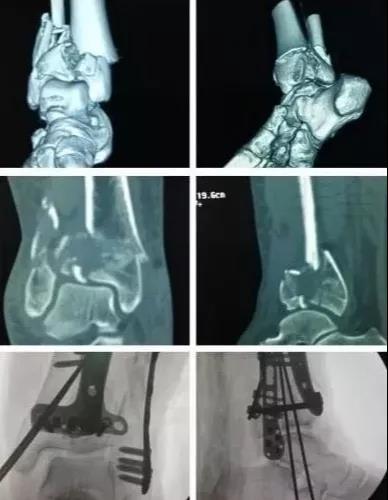

7)胫骨远端(pilon,踝部)

- pilon骨折,高能损伤,6-8h肿胀未形成,可以急诊做,手术时间<3小时。

- 10-14天,分步延期手术策略。

- 踝部骨折手术时机同样取决于皮肤条件。

8)足部骨折(距骨,跟骨,跖骨等)

高能损伤导致的距骨骨折并脱位,建议急诊做。